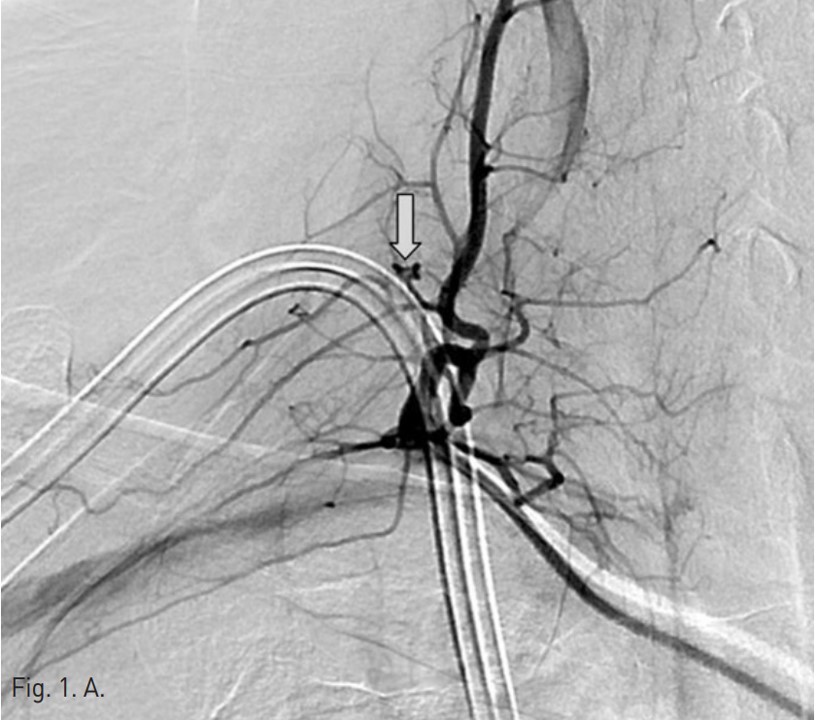

Permanent catheter insertion 이후 일주일 뒤 시행한 혈관조영술에서 갑상목동맥(right thyrocervical trunk)의 branch에 작은 거짓동맥류(small pseudoaneurysm)가 있고 permanent catheter를 insertion하는 과정에서 비롯된 합병증으로 판단되었음(Fig. 1A,B). 따라서 갑상목동맥의 기시부에서부터 아래 갑상동맥(inferior thyroidal artery)의 기시부까지 색전술을 시행하기로 함. Microcoil 및 glue를 사용하여 embolization 시행 후 조영제 검사에서 거짓동맥류는 보이지 않고(Fig. 2A,B) 임상 소견도 모두 호전되었음.

오른쪽 서혜부를 국소 마취 후 오른쪽 대퇴동맥을 천자하여 대동맥으로 카테터삽입술을 시행함. 그 후 guidewire를 통해 오른쪽 쇄골하 동맥 (right subclavian artery) 으로 진입하였고 조영술을 시행하여 갑상목동맥의 한 분지에 작은 거짓동맥류가 있는 것을 확인하였음(Fig. 1A,B). 이어서 2.2-F microcatheter with microwire(Progreat catheter, 150cm and Gold tip wire, Terumo)를 이용하여 거짓동맥류가 있는 분지로 진입하려 하였으나 혈관의 tortuosity가 심하여 시행하지 못함. 그래서 아래 갑상동맥의 기시부에서부터 갑상목동맥의 기시부까지 색전술을 시행하기로 하였고, microwire(Fathom, 0.016 inch, 160 cm, Cook)를 이용하여 아래갑상동맥으로 진입함.

Fig. 1. Selective angiography of the right thyrocervical trunk shows a pseudoaneurysm(arrow) from a branch of the right thyrocervical trunk.